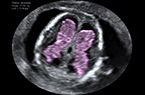

Coupe classique des 4 cavités cardiaques - foetus de 36 SA Coupe classique des 4 cavités cardiaques - foetus de 36 SA Coupe classique des 4 cavités cardiaques - foetus de 36 SA

Coeur foetal - Coupe des quatre cavités cardiaques - 33 SA Coeur foetal - Coupe des quatre cavités cardiaques - 33 SA Coeur foetal - Coupe des quatre cavités cardiaques - 33 SA